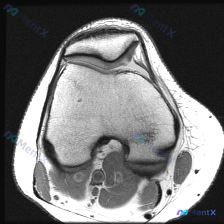

看到这个病例,临床关注点是「膝关节软骨异常」,只拿到了这一张膝关节MRI T1加权轴位图像,整理一下分析思路给大家参考。

这是一张股骨远端层面的轴位T1加权图像,先整理一下能看到的信息:

- 骨结构:股骨内侧髁、外侧髁轮廓清晰,皮质骨连续低信号,骨髓腔内中等信号符合正常表现,滑车沟形态可见

- 髌股关节软骨:髌骨位于滑车沟前方,形态大致正常,髌股关节间隙存在,关节软骨厚度均匀,没有看到明显的局限性缺损或剥脱

- 周围软组织:股四头肌肌腱、股内侧肌、股外侧肌信号正常,没有肌肉萎缩或脂肪浸润;腘窝血管神经束可见,没有异常占位

- 关节腔:髌股关节及周围滑膜隐窝没有异常扩张积液,T1序列未见异常信号

整体从这张图像上,没有看到明确的骨质破坏、软组织肿块或者明确的异常信号。